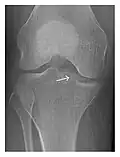

Figure 6: Subtle anterior talar fracture in a 39-year-old man presenting with ankle pain after a fall. (a) Anteroposterior radiograph shows a subtle oblique radiolucent line through the talus (white arrows). (b) Sagittal CT reformation confirms the presence of an anterior talar fracture with cortical offset (black arrow). Avulsion fractures, which consist of a detached bone fragment resulting from a ligament or tendon pulling away from the bone, may also present with subtle radiographic signs. Tiny osseous fragments near the presumed attachment site of a ligament suggest this diagnosis. Common sites are the lateral tibial plateau (the Segond fracture), the spinal tuberosity of the tibia resulting from anterior cruciate ligament avulsion, and the ischial tuberosity.[1]